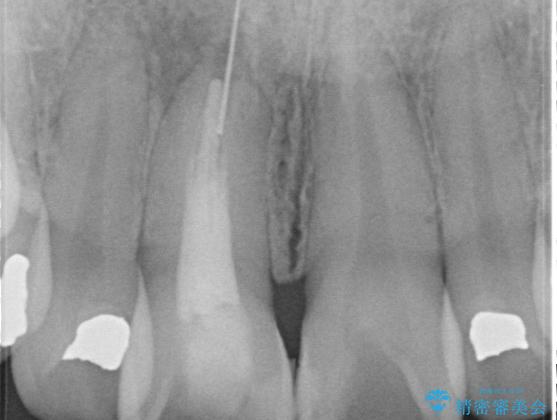

器具が破折して残ったままの前歯

お痛みは無く、たまに異和感があるとのことでレントゲン撮影をすると、以前根の治療をされた際の器具が破折したまま残っていました。

破折した器具を除去したのち、根管治療、ファイバーコア築造、セラミッククラウンの製作を行いました。

歯の根に器具が残っている事にビックリされていました。